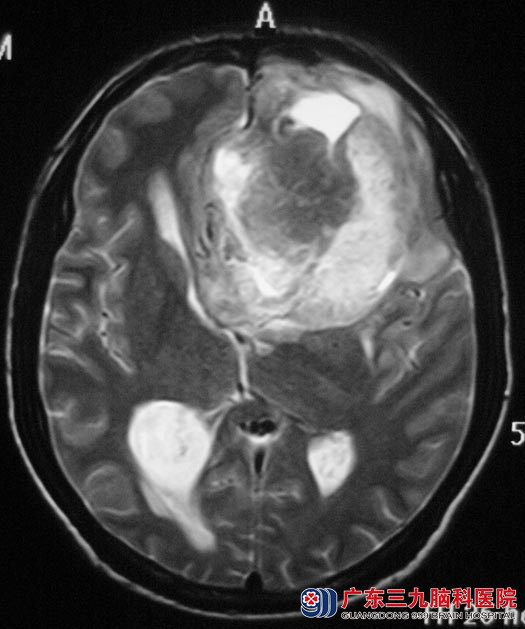

当地医院CT结果提示:左侧额叶占位性病变,考虑胶质瘤的可能。

入住广东三九脑科医院综合神经外科,完善相关检查后,鲁明主任主刀,在全麻下行左侧额叶肿瘤切除+去骨瓣减压术,术中见肿瘤呈胶冻样,质地硬,血供丰富,左侧大脑前动脉被肿瘤包裹,显微镜下予肿瘤分块切除,术后病理证实为:左侧额叶胶质母细胞瘤(WHO IV级)。之后梁老师还需要进一步的放化疗。